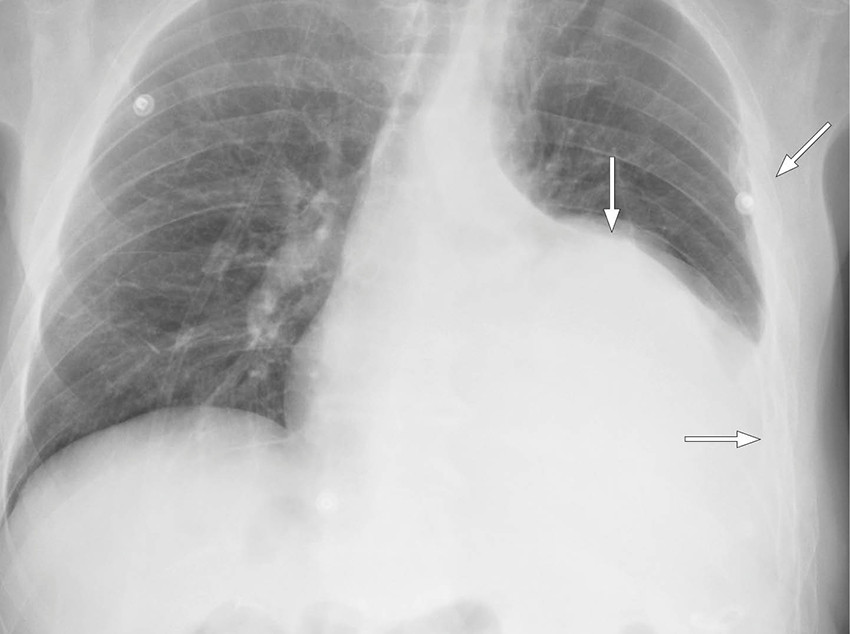

Etter to dagers behandling med alteplase ble pasienten utilpass med smerter i venstre hemithorax. Symptomene lettet da han la seg i sengen. Det ble like etterpå målt blodtrykk på 130/80 mm Hg, puls på 70 slag/min, perifer oksygenmetning på 97 % og registrert 400 mL blodig væske i drenposen. Noen timer senere ble pasienten igjen utilpass, og det ble målt blodtrykksfall til 55/30 mm Hg. Kontroll av hemoglobin viste et fall fra 9,4 til 8,2 g/dL i løpet av dagen. Tilstanden stabiliserte seg med intravenøs væskebehandling og en enhet erytrocytter. Pasienten var våken og blek, og blodtrykket var 100/60 mm Hg. Røntgen thorax viste tiltagende pleuraeffusjon (figur 1), og påfølgende CT thorax konstaterte massiv hemothorax med forskyvning av mediastinum samt en blødningssuspekt lesjon i relasjon til diafragma (figur 2). Tilbake på avdelingen hadde pasienten tiltagende takykardi med puls på 118 slag/min. Blodtrykket var 110/72 mm Hg. Det ble lagt et 28 french-pleuradren akutt og tappet én liter blod.

Ved videoassistert torakoskopi samme kveld fant man anterolateralt blødende oment gjennom en defekt i diafragma. Torakoskopisk fjernet man det blødende omentet og lukket defekten. Pasienten ble samtidig laparoskopert uten funn av ytterligere lesjoner i abdomen. Det postoperative forløpet var ukomplisert, og pasienten ble utskrevet i velbefinnende syv dager etter inngrepet.

I denne kasuistikken ga behandlingen vesentlig forverring av pasientens tilstand før den tilgrunnliggende årsaken ble identifisert og korrigert. Fibrinolysebehandling ble foretrukket på grunn av tiden siden traumet og pasientens klinisk stabile tilstand og betydelige komorbiditet, herunder diabetes og pankreatitt. Ved gjennomgang av CT-bildene fra den første innleggelsen og de senere røntgenbildene ses ikke tegn til diafragmaruptur. Diagnosen er sjelden og kan være klinisk og radiologisk vanskelig å stille, men bør overveies hos pasienter med relevant høyenergitraume (3).